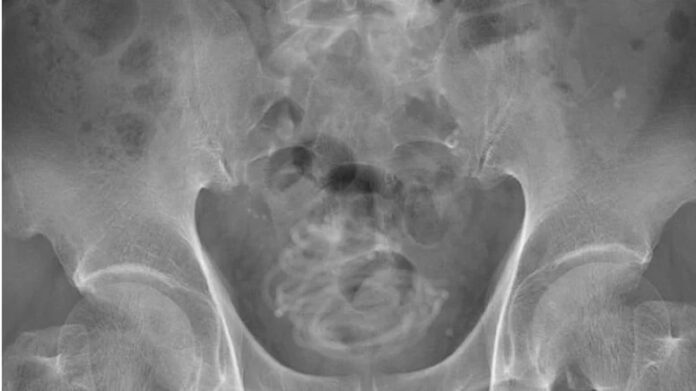

Röntgen çekildikten sonra adamın penisinden içeri atlama ipi yerleştirildiğini gören doktorlar şaşkına döndü. İngiliz medyasında yer alan haberlerde hastane çalışanları, “Kariyerimiz boyunca bu kadar aşırı bir şey görmedik” açıklamasını yaptı.

Yapılan zorlu bir ameliyat süreci sonrasında adamın penisinden atlama ipinin çıkarıldığı belirtildi. Atlama ipinin tutma kısımlarının olmadığı ve 2 metreden uzun olduğu belirtildi. İpin, idrar torbasında düğüm olduğu ve bu sebeple ameliyatın riskli geçtiği de belirtildi.

İpin ince olduğuna dikkat çeken doktorlar, ipin düğüm olması sebebiyle idrar torbasına bir delik açarak cerrahi bir müdahale gerçekleştirildiğini de duyurdu. Ameliyatın başarılı geçmesi için idrar torbasının 3-D modelinin yapıldığı ve bu sayede doktorların nasıl müdahale edeceklerinin anlaşıldığı açıklandı.